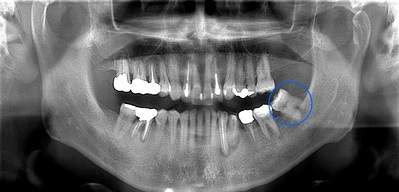

右下奥歯が痛い症例

- 抜歯前写真(レントゲン)

| 年齢 | 40代・男性 |

|---|---|

| 主訴 | 右下奥歯が痛い |

| 親知らずの生え方 | 斜めに生えている |

| 抜歯時間 | 30分 |

| 費用 | 約6,000円(保険診療、CT代含む) |

| 抜歯内容 | レントゲン上で右下の親知らずが大きく虫歯になっており、斜めに生えていることもあり患者様の希望により抜歯することとなりました。 当日は痛みがあったため抗生剤と鎮痛剤にて炎症を抑え、後日歯ぐきを切開し、抜歯を行いました。 レントゲン上でも分かるように親知らずの根が二つに分かれており根が折れてしまう可能性がありましたが、このケースでは事前にCTを撮影し、歯の位置、根の方向を確認していたため根が折れることなく抜歯ができました。 術後数日は腫れと痛みがありましたが、薬の服用で抑えることができ、1週間後の糸取りの際には痛み、腫れともになくなっていました。 |